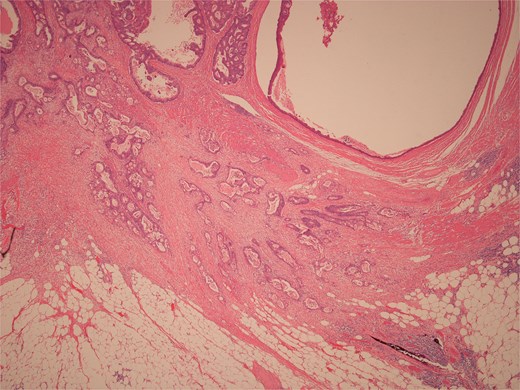

Histopathological examination of surgical specimens revealed three distinct neoplasms: (i) invasive colonic adenocarcinoma (Figs 4 and 5), (ii) jejunal NET (Figs 6 and 7), and (iii) small-lymphocytic lymphoma (Figs 8 and 9). Morphological assessment supported by immunohistochemical profiling confirmed each represented an independent primary, with no evidence of a shared clonal origin. The findings were subsequently reviewed at the Multidisciplinary Meeting alongside Oncology and Haematology specialists, and adjuvant single-agent chemotherapy was initiated, with planned surveillance of the indolent lymphoma.

Low power view of colonic adenocarcinoma invading muscularis propria and pericolonic fat.